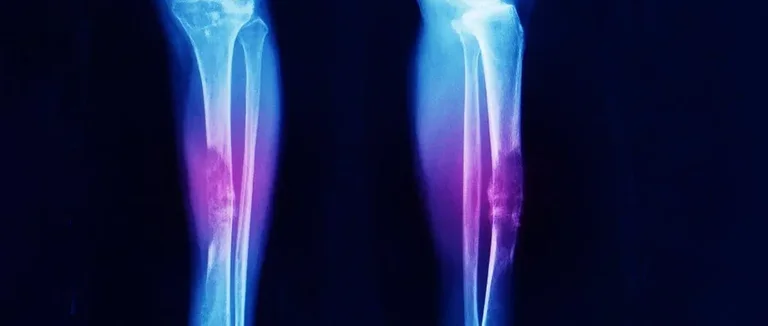

Les os des jambes, du bassin et de la paroi thoracique sont souvent touchés par le sarcome d'Ewing. Ce cancer osseux préfère certaines zones du corps. Cela peut changer le diagnostic et le traitement.

Os longs des jambes et des bras

Le sarcome d'Ewing aime les os longs des jambes et des bras. Le fémur et l'humérus sont des endroits communs pour cette tumeur. Ces zones peuvent causer des douleurs et des gonflements, les premiers signes.

Les os longs sont souvent touchés. Cela vient de leur structure et de leur rôle. Voici les os longs les plus touchés :

| Tibia | Jambe | Modérée |

Os plats : bassin, côtes et omoplates

Le sarcome d'Ewing peut aussi toucher les os plats comme le bassin, les côtes et les omoplates. Ces endroits peuvent causer différents symptômes selon la taille et la position de la tumeur.

Par exemple, une tumeur dans le bassin peut causer des douleurs abdominales ou des problèmes de marche. Comprendre ces différences est crucial pour un bon diagnostic et traitement.

En bref, le sarcome d'Ewing peut se développer dans plusieurs endroits, surtout dans les os longs et les os plats. Reconnaître ces zones est essentiel pour bien soigner la maladie.

Les premiers pas pour diagnostiquer le sarcome d'Ewing sont les examens d'imagerie. Nous faisons des radiographies, des IRM et des CT scans. Ces outils nous montrent la tumeur et sa taille.